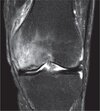

Figure 1 is the MRI scan of a 15-year-old boy who has had knee pain with running for 5 months. What is the most appropriate treatment?

Arthroscopic or open reduction and internal fixation ## Footnote OCD is an acquired lesion of the subchondral bone. Patients with OCD initially report nonspecific pain and variable amounts of swelling. **Initial radiographs help identify the lesion and establish the status of the physes**. An MRI scan is useful for assessing the potential for the lesion to heal with nonsurgical treatment. **Nonsurgical treatment is appropriate for small, stable lesions in patients with open physes and focuses on activity restriction for 3 to 9 months**. Surgical treatment is necessary for unstable or detached lesions. Stable lesions with intact articular cartilage can be treated with subchondral drilling to stimulate vascular ingrowth, with radiographic healing at an average of 4.4 months. Fixation is indicated for unstable or hinged lesions, and stabilization of the fragment can be achieved using a variety of implants through an arthroscopic or open approach. The fragment should be salvaged and the normal articular surface restored whenever possible.